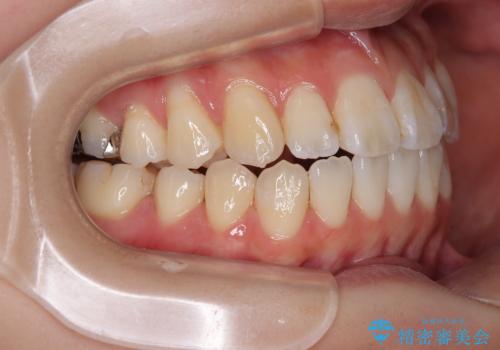

舌の突出癖が原因 インビザライン矯正による開咬改善

- 前歯の開咬を気にして来院された患者様です。

開咬の治療は、前歯を閉じるように動かすとともに、上下臼歯を圧下(骨内にめり込ませる)させることで進めて行きます。

インビザラインは臼歯の圧下を効果的に行えるため、インビザラインを用いて矯正治療を行うこととしました。

オープンバイトは舌の突出癖により誘発され、治療後も突出癖が残っている容易に後戻りしてしまいます。

治療期間を短縮するためにも、舌突出癖の改善が極めて重要となります。

特にインビザラインではIPRという歯と歯の間を削る処置を多用するため、後戻りによりスペースが生じやすくなるため、治療初期段階での舌のトレーニングが必須となります。